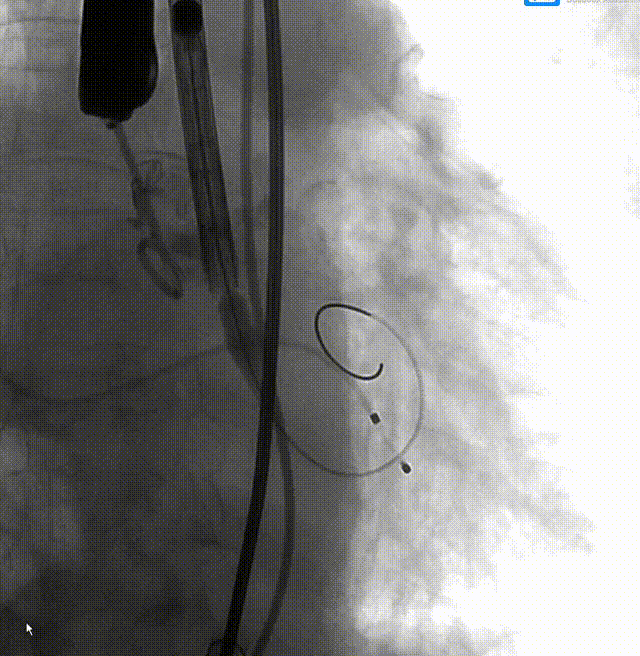

TaurusElite 输送器轻松过弓、跨瓣,TaurusElite AV26精准定位无冠窦最低点。

TaurusElite柔顺过弓

瓣膜定位